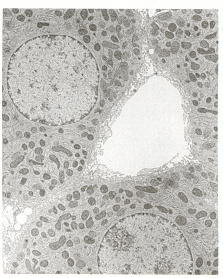

Electron Micrograph of Liver Cells (5)

“The metabolic activities of the liver are essential for providing fuel to the brain, muscle, and other peripheral organs.”